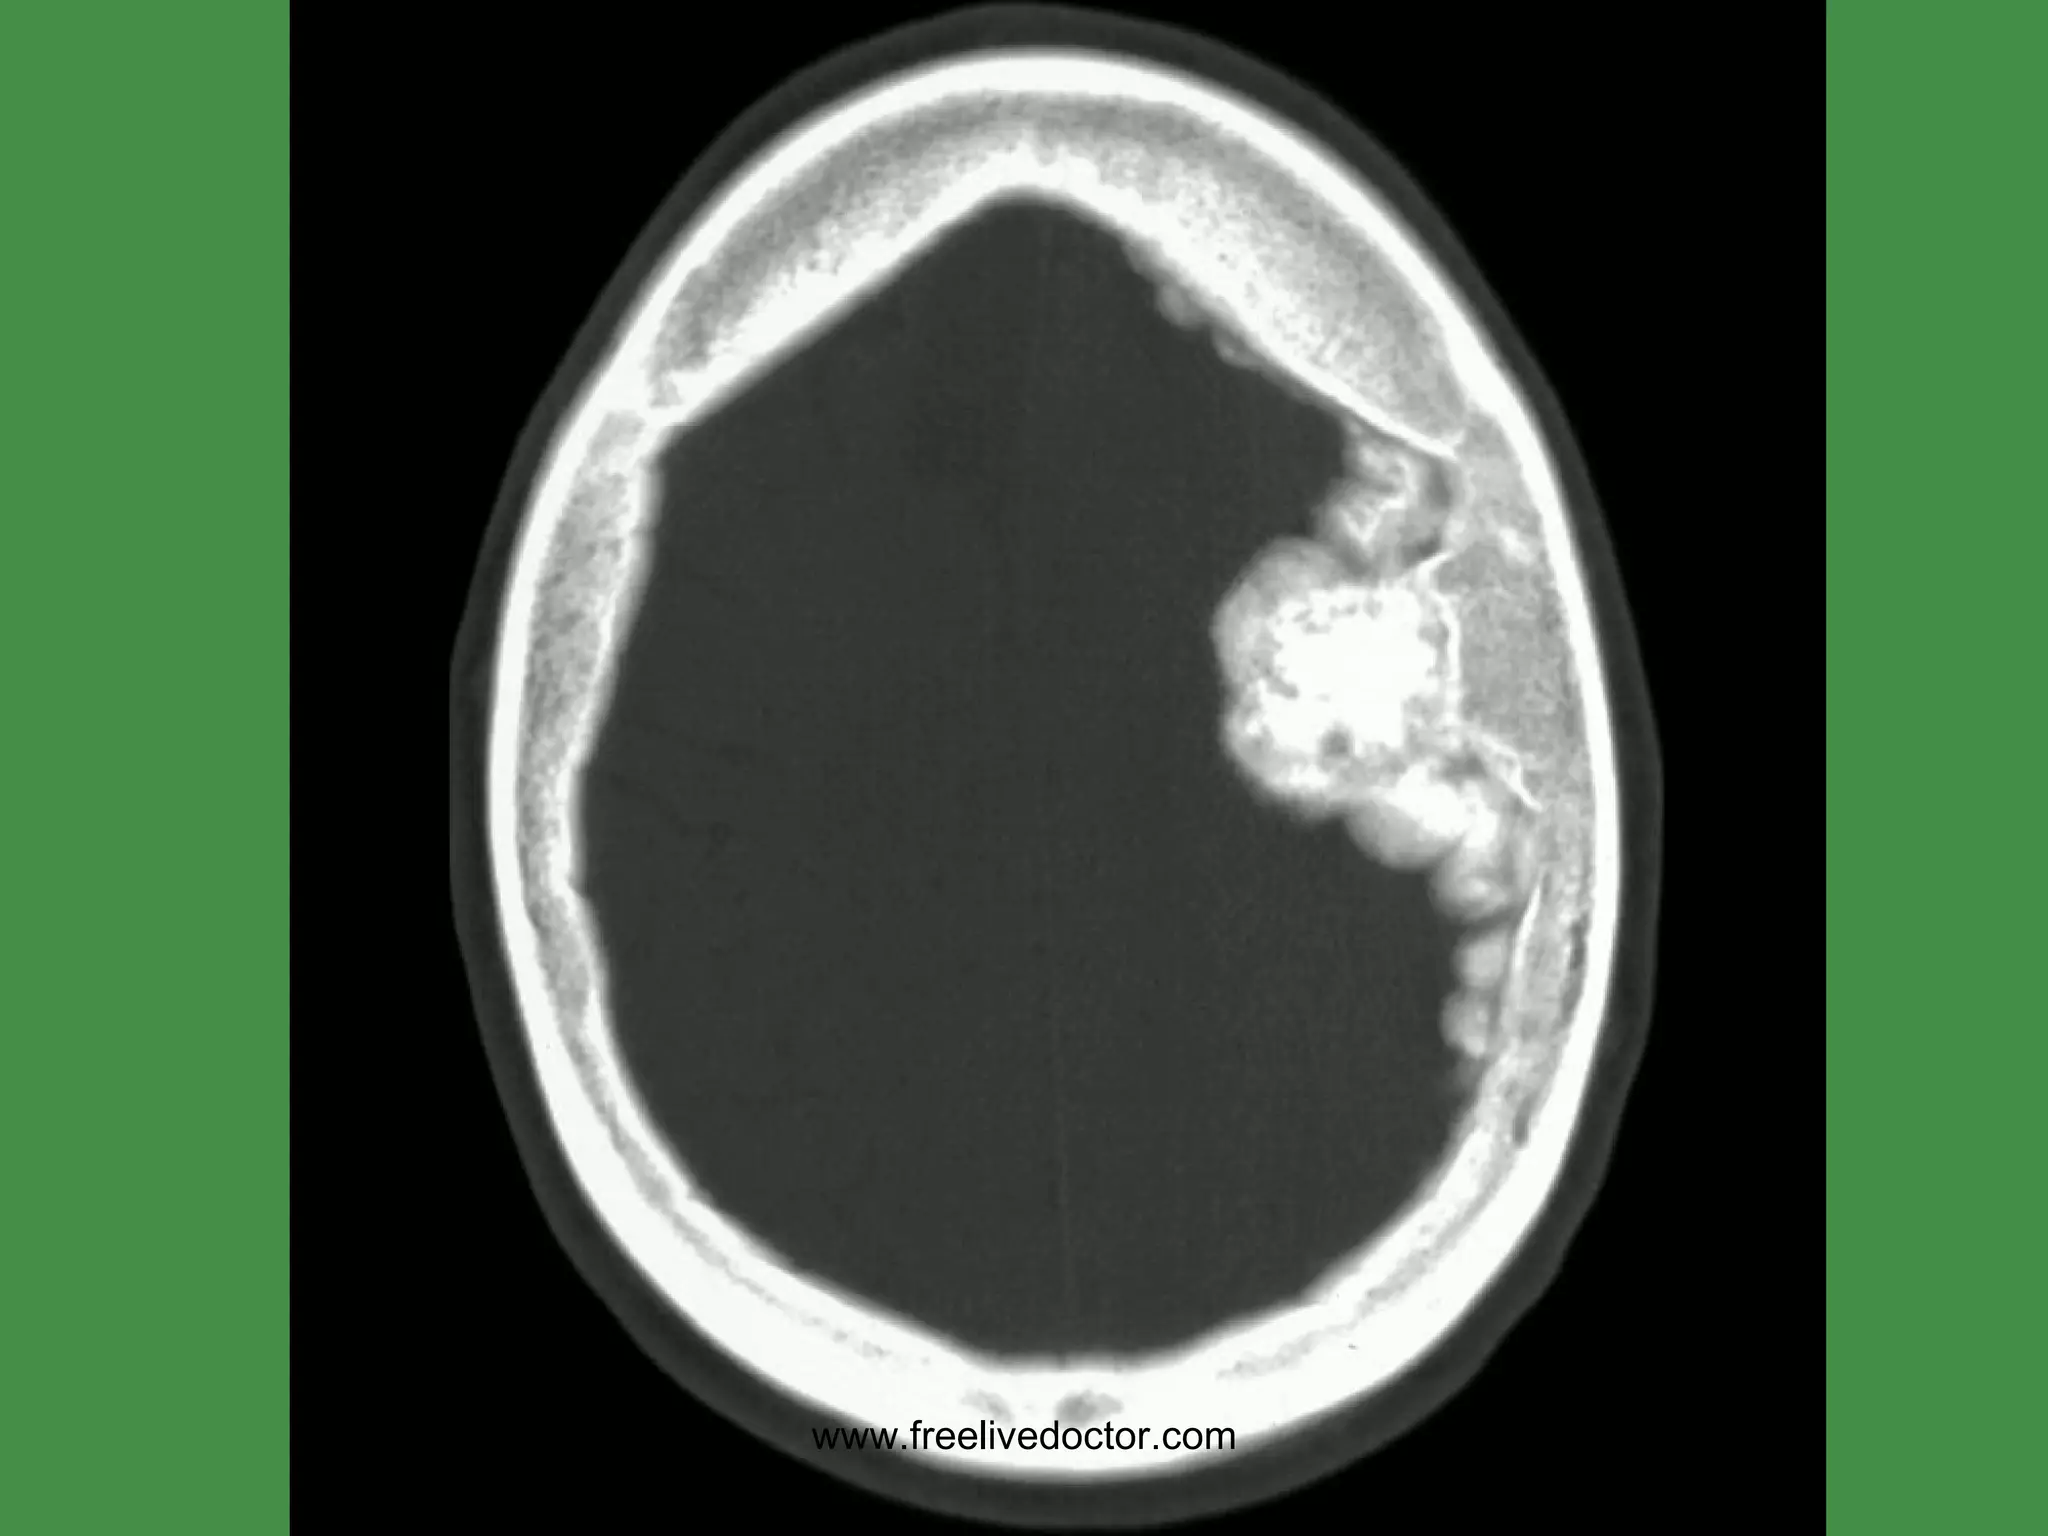

MENINGIOMAS Occur where dura is Very vascular BENIGN, but…. Can invade skull, etc. Only invade (displace) brain in areas adjacent to dura, i.e., parasagittal, falx, tentorium, venous sinuses Small, firm, and well defined like a SUPERBALL Often (usually?) have  PSAMMOMA   bodies www.freelivedoctor.com

• #162 Arts of this meningioma are denser than bone.

• #163 Note cortical compression from this meningioma.